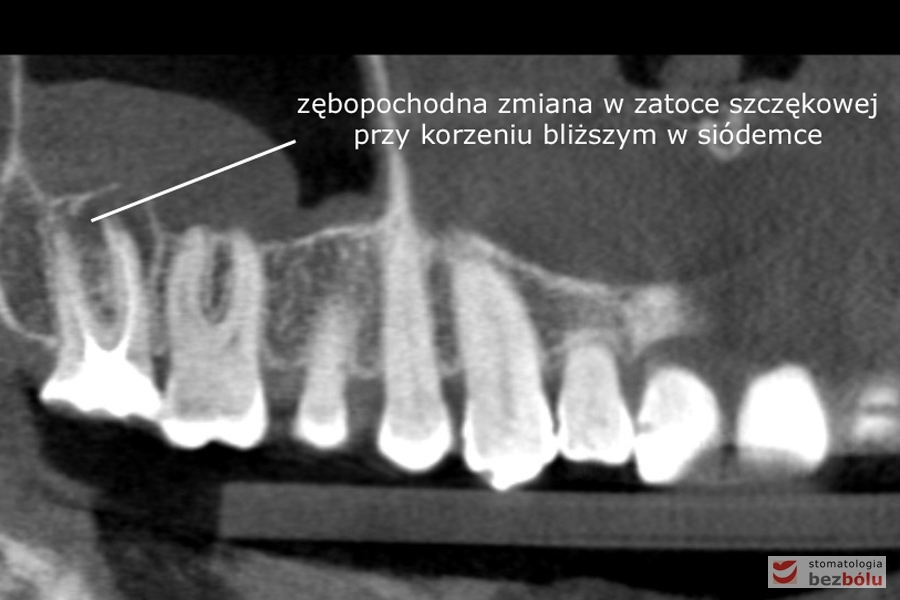

Diagnostyka radiologiczna - ocena zmian zapalnych w obrazie tomografii wolumetrycznej

Diagnostyka radiologiczna – ocena zmian zapalnych w obrazie tomografii wolumetrycznej